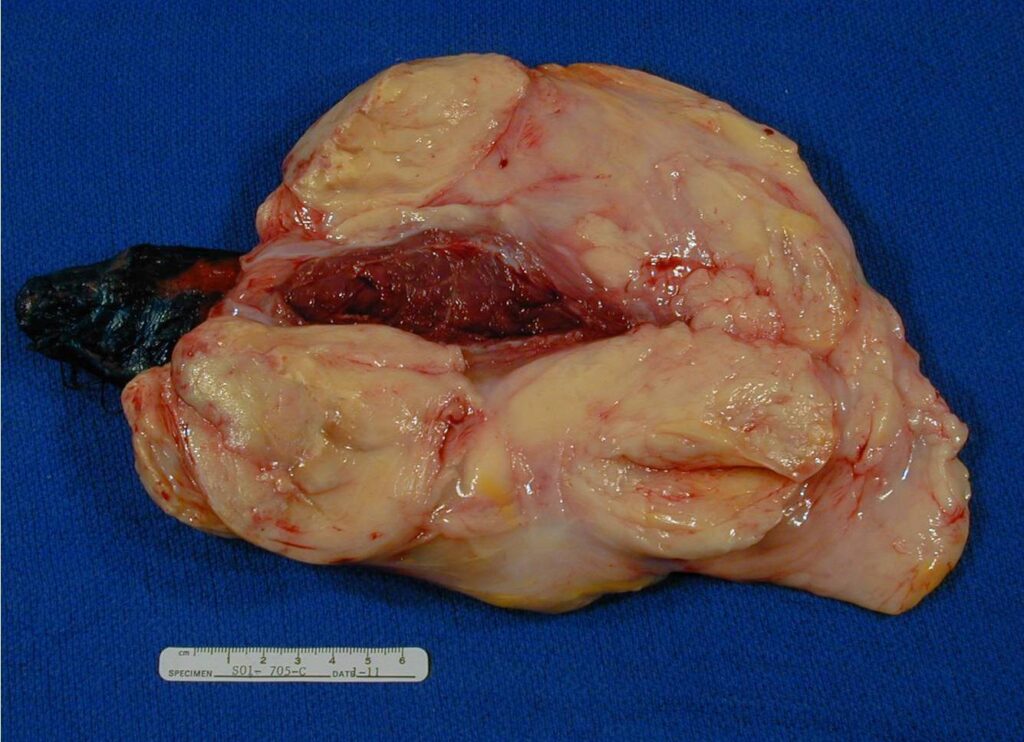

PATHOLOGY

Multinodular growth within and between skeletal muscle

• Soft and pale yellow on cut

• Surgery is the mainstay of treatment. The most reliable means of obtaining local tumor control is by surgical excision with a wide excision if possible however most are marginally excised. (Fig. 9-13)

Fig. 9-13 Intraoperative. Wide Resection of an intermuscular Well Differentiated Liposarcoma.